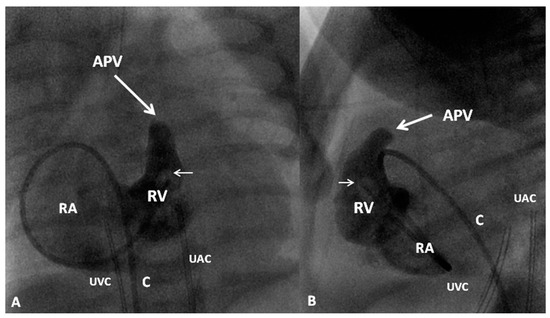

If the RV is of reasonable size and tripartite or bipartite in nature (Figure 14), trans-catheter perforation with radiofrequency wire (Figure 15) followed by balloon valvuloplasty is performed to restore RV to PA continuity (Figure 16 and Figure 17).